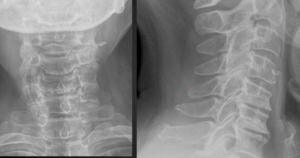

1. The Pseudofracture Appearance of Uncovertebral Arthrosis

In the lateral view of figure 1, note the horizontal radiolucent line through C5 and C6. This finding is often mistaken for a fracture on radiographs. The AP radiograph nicely demonstrates uncinate process hypertrophy at C6 and C7. The degenerative hypertrophy of the uncinate processes causes an abnormal pseudoarthrosis to form between the uncinate process below and the inferior vertebral body above. This pseudoarthrosis results in the horizontal radiolucency seen traversing the vertebral body.